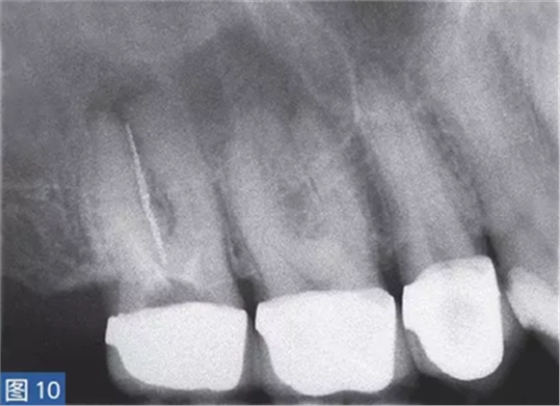

慢性根尖周膿腫(圖10 和11)是由長期持續(xù)的炎癥引起的。膿液穿通骨和口腔黏膜,并通過口腔黏膜或上皮的瘺管流出。這些通到表皮的瘺管通??赡茏鳛槠つw損傷而被錯(cuò)誤處置。此外,瘺管也可能存在于牙周并通過齦溝引流。瘺管可以部分或完全地被上皮所包繞,這些上皮又被炎性結(jié)締組織包圍。

臨床診斷顯示牙髓電活力測(cè)試結(jié)果為陰性。除非瘺管閉合,否則叩診和觸診通常都不會(huì)引起疼痛。放射學(xué)檢查,根尖周組織表現(xiàn)從無變化到發(fā)生明顯變化。

圖10:17 牙齒CAA。術(shù)前放射學(xué)檢查,利用牙膠尖顯示瘺管?;颊咭?7 牙齒局部瘺管而前來就診,訴無特殊臨床癥狀。

圖11: 17 牙齒CAA。根管治療12 個(gè)月后。